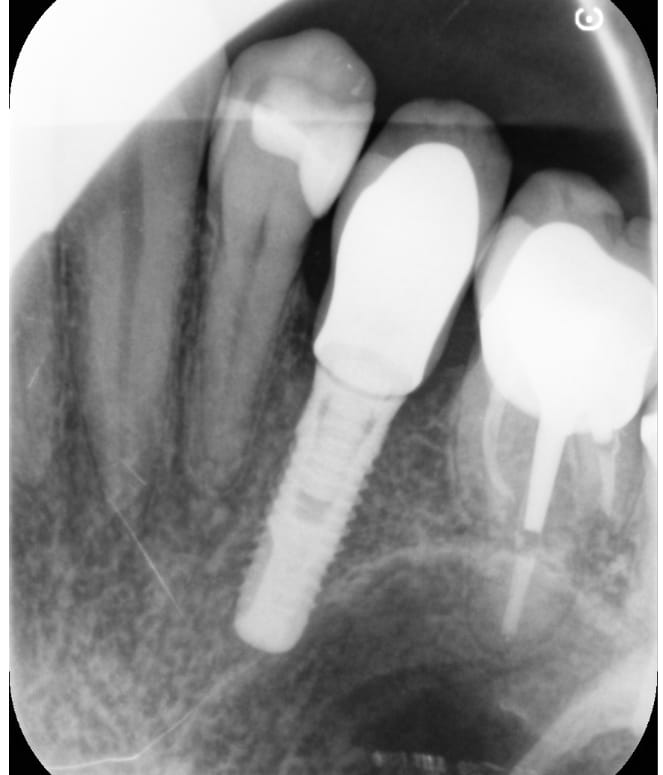

J'ai besoin d'identifier cet implant.

Serf EVL N ( Global D maintenant)